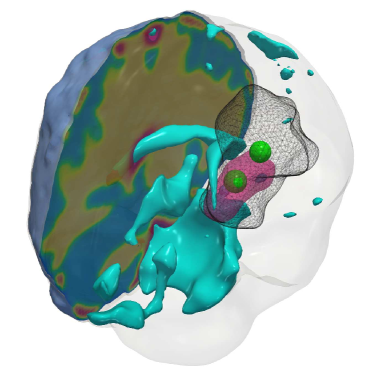

Fig. 4: (a) Description of the visualized brain sub-structures: The figure on the left shows an isometric view of the brain with different tumorous and healthy tissue sub-structures. The figure on the right zooms in on the tumor region and describes each structure. (b, c) Qualitative results for the artificial tumor test-case AT-C1 (a mono-focal, mostly proliferative tumor) with growth parameters ρ=8,κ=0.025formulae-sequencesuperscript𝜌8superscript𝜅0.025\rho^{\star}=8,~{}\kappa^{\star}=0.025. The images show the tumor data (gray wireframe), ground truth tumor initial condition (green volume), reconstructed tumor initial condition (magenta volume), ventricles (cyan volume), and a section of the patient brain geometry. We observe exact reconstruction for smaller tumors with sparsity constraints. The \mathboldL2\mathboldsubscript𝐿2\mathbold{L_{2}} solver fails to obtain the same reconstruction due to its inability to determine the correct reaction coefficient. We refer the reader to Tab. 4 for the quality of final tumor reconstruction.

Setup. We grow synthetic tumors in the segmentation of a statistical brain atlas [8] MRI scan (an atlas obtain by averaging several MR images). The segmentation labels are gray matter, white matter, and cerebrospinal fluid-filled ventricles (CSF). We use sparse initial conditions to grow the tumor to a significant size resembling clinical observations and invert for all biophysical parameters using the grown tumor at t=1𝑡1t=1 as input data to the solver. For all our test cases, we assume that the tumor grows and diffuses only in white matter. For this test-case, we observe the data everywhere, i.e., cd=0subscript𝑐𝑑0c_{d}=0. We consider the following variations:

(i) AT-C1: medium sized, mono-focal tumor ρ=8superscript𝜌8\rho^{\star}=8 κ=0.025superscript𝜅0.025\kappa^{\star}=0.025

(ii) AT-C2: large sized, mono-focal tumor ρ=12superscript𝜌12\rho^{\star}=12 κ=0.05superscript𝜅0.05\kappa^{\star}=0.05

(iii) AT-C3: multi-focal tumor, nearby seeds ρ=10superscript𝜌10\rho^{\star}=10 κ=0.025superscript𝜅0.025\kappa^{\star}=0.025

(iv) AT-C4: multi-focal tumor, distant seeds ρ=8superscript𝜌8\rho^{\star}=8 κ=0.025superscript𝜅0.025\kappa^{\star}=0.025

We report our quantitative results (performance measures, convergence, and solver timings) in Tab. 4 and visualize the reconstruction to qualitatively assess the performance of our solvers in Fig. 4 - Fig. 7. Each figure shows an isometric view of the patient brain with 3D volumes of the grown tumor data, ground truth, and reconstructed initial condition. We additionally visualize the ventricles and sections of healthy tissue to reveal the heterogeneity of the brain (and hence the tumor).

Observations. We observe that for the medium sized tumor (AT-C1) the reconstruction is nearly perfect for the CS solver while the \mathboldL2\mathboldsubscript𝐿2\mathbold{L_{2}} solver produces a lower performance, particularly in the inversion of the reaction coefficient. This is primarily due to the rich initial conditions produced by the \mathboldL2\mathboldsubscript𝐿2\mathbold{L_{2}} solver which impedes its ability to predict the correct reaction scaling using our method. We note that if the reaction scaling is known beforehand, the \mathboldL2\mathboldsubscript𝐿2\mathbold{L_{2}} solver can potentially have better performance (see [56, 16] for similar synthetic experiments). This problem is magnified for larger tumors (AT-C2 and AT-C3) where the predicted reaction coefficient shows about 66%percent6666\% and 54%percent5454\% relative error in the \mathboldL2\mathboldsubscript𝐿2\mathbold{L_{2}} solver for the two test-cases respectively (as compared to around 15%percent1515\% and 1%percent11\% error with sparsity constraints). The reconstruction in diffusivity also suffers similarly without enforcing sparsity. The final test-case shows a multi-focal tumor with two far apart proliferation sites. While both the solvers produce disjoint initial conditions for the tumor, the CS solver does better in reconstructing the model parameters: 2% versus 37% relative error in diffusivity and 9% versus 50% relative error in reaction coefficient. Both solvers show similar performance in their ability to fit the data (as measured by the relative error in final tumor reconstruction). Hence, our synthetic observations show consistent improvement in target parameter estimation for all test-cases with sparse initial conditions, without sacrificing the final tumor reconstruction quality.